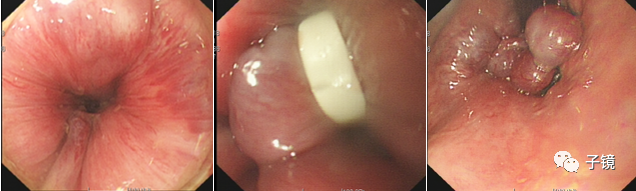

9) 胶圈套扎术(RBL)1954年,Blaisdell 首用套扎法治疗内痔1962年,由Barron 进行了改进并报道了痔胶圈套扎的良好疗效,是目前公认最有效的方法2008年,ElNakeeb AM等人发表的RBL连续治疗750例Ⅱ度和Ⅲ度痔的病例系列研究显示,随访2年后治愈率为93%、复发率为11% ,且不受痔的分度影响;以肛垫下移学说为理论基础而设计的一种痔的治疗方法,更符合痔的现代治疗原则;COOK痔疮枪技术是目前国际上非常高效的套扎技术,采用天然橡胶套扎环,以0.1MPa的压力不间断吸引病灶处,在极短时间达到吸引部位组织分离、坏死、干结、继而脱落、当痔疮脱落的瞬间压力吸引自动停止。

A、原理套扎后粘膜皱缩,肛垫上提;局部炎症反应致使粘膜、粘膜下层与浅肌层粘连,肛垫固定于较高位置部分阻断痔疮血供或减少静脉倒流,减少痔的充血肥大或血流淤滞,使痔块萎缩直接套扎痔块基底部,可即刻止血

B、适应证:各期内痔(I~III期效果最好)、混合痔内痔部分、对PPH或其他疗法后痔块或肛垫回缩不全者,可采用RBL作补充治疗;其他:直肠局灶性病变,如直肠息肉、直肠血管瘤或血管畸形等。